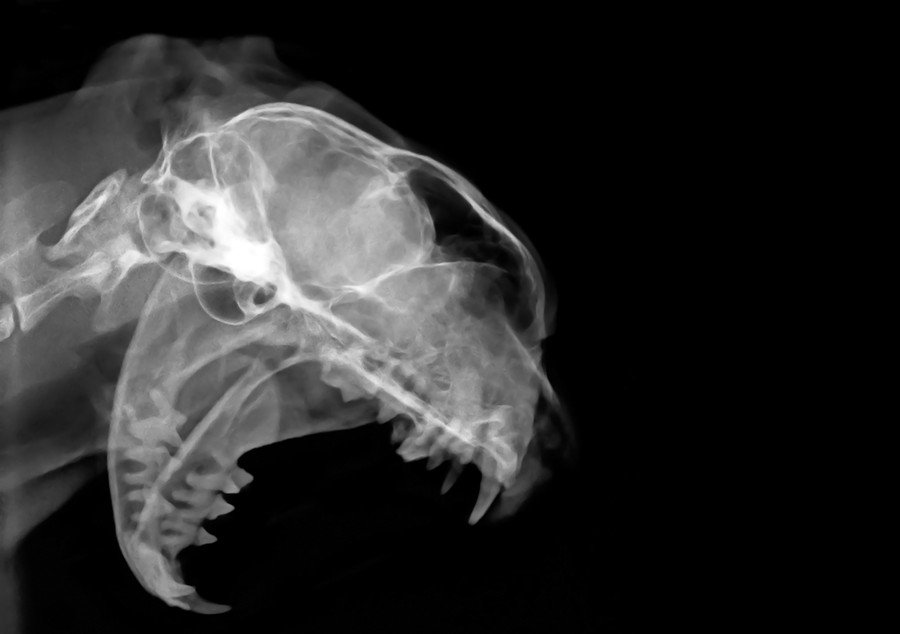

画像はイメージです